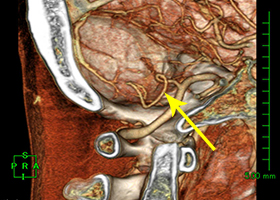

53歳女性、左舌咽神経痛

[画像所見]

-

頭部MRI -

頭部造影三次元CT

左後下小脳動脈が左舌咽神経を圧迫していたために左咽頭部を中心に激しい痛みが生じていました。

術前造影三次元CT -

術後造影三次元CT

左後下小脳動脈(黄色矢印)は術後に本来の位置から移動している。舌咽神経への血管圧迫が解除されたため、術後に患者様は舌咽神経痛が消失した。